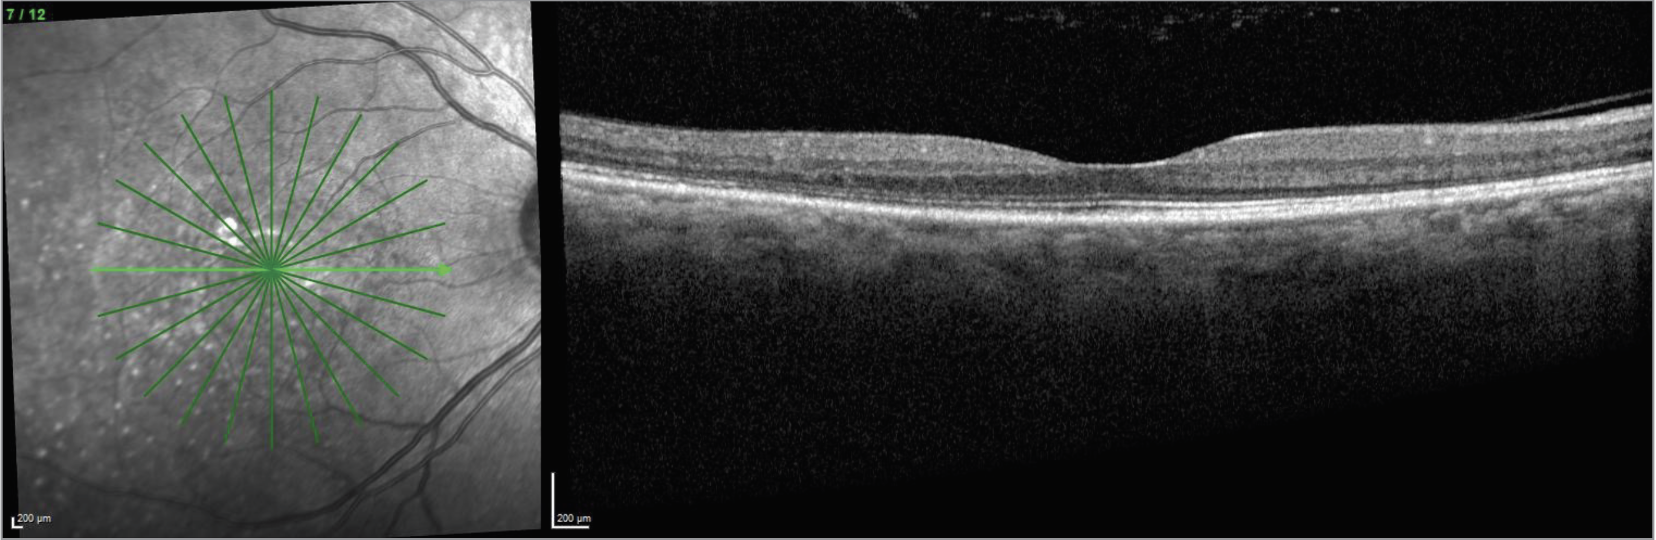

| Figure 6. OCT of the left eye revealing mixed subretinal fluid and bacillary detachments. |

In this case, the presence of a bacillary detachment was critical for making the diagnosis of VKH in a timely manner. “Bacillary” means “shaped like a rod”; a bacillary layer detachment is named as such because photoreceptors are approximately rod-shaped, and the detachment involves splitting of the photoreceptors at the level of the inner segment myoid. It can be recognized on OCT as fluid between the ellipsoid zone and the external limiting membrane.

In terms of mechanism, one hypothesis is that a bacillary layer detachment occurs when the accumulation of subretinal fibrin modulates the adhesion between the photoreceptor outer segments and the apical microvilli of the retinal pigment epithelium.6 Subretinal exudation then exerts hydrostatic pressure, leading to the bacillary layer detachment.